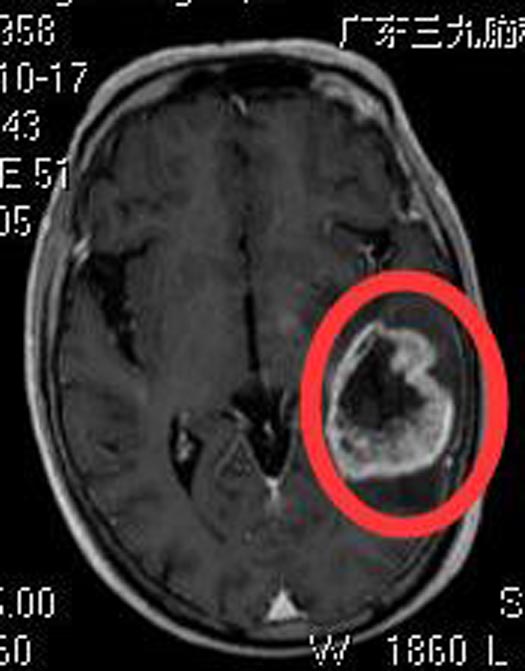

一个月前,潘爷爷出现咳嗽、感冒症状,伴头晕、头顶胀痛,间断低热,就近诊所治疗后,症状无明显改善。当地医院头颅CT检查提示颅内占位,广东三九脑科医院头颅MR检查显示:左侧颞叶占位性病变,大小约4.6cm×3.8cm×3.4cm,考虑胶质瘤可能性大。

术前